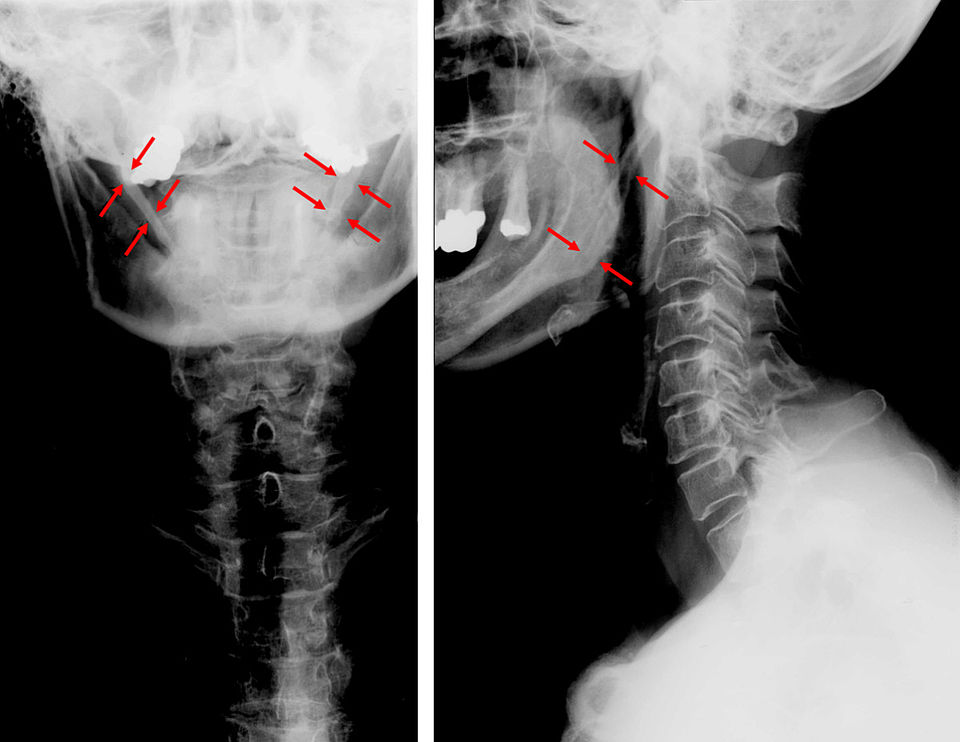

The doctor suspected I have something called Venous Eagle Syndrome. Eagle Syndrome is a rare syndrome (about 0.16% of the population has it) where a needle-like bone near the ear called the styloid process is too long, or the stylohyoid ligament is calcified and rigid and presses on something, often the throat, causing issues with swallowing or speaking. But a subtype of Eagle Syndrome has it pressing either on the carotid artery or, suspected in my case, on my internal jugular vein. This is also called styloidogenic jugular venous compression syndrome, which, in medical speak, literally means the jugular vein is compressed by the styloid.

In order to test for Venous Eagle Syndrome, the doctor sent me for a CT of my head and neck with contrast, and the results were pretty conclusive: I have an elongated styloid process—mine is 33 millimeters (25–30 mm is normal)—and it is pressing on my jugular vein on both sides. I have pulsatile tinnitus, one of the symptoms of Venous Eagle Syndrome, and it stops when I press on my jugular, which is further evidence that this is the reason for my symptoms. I am now waiting for an appointment with the one doctor in my country who works with Venous Eagle Syndrome and have connected with a WhatsApp group of about 25 people in my country with Eagle Syndrome to discuss what my next steps should be.